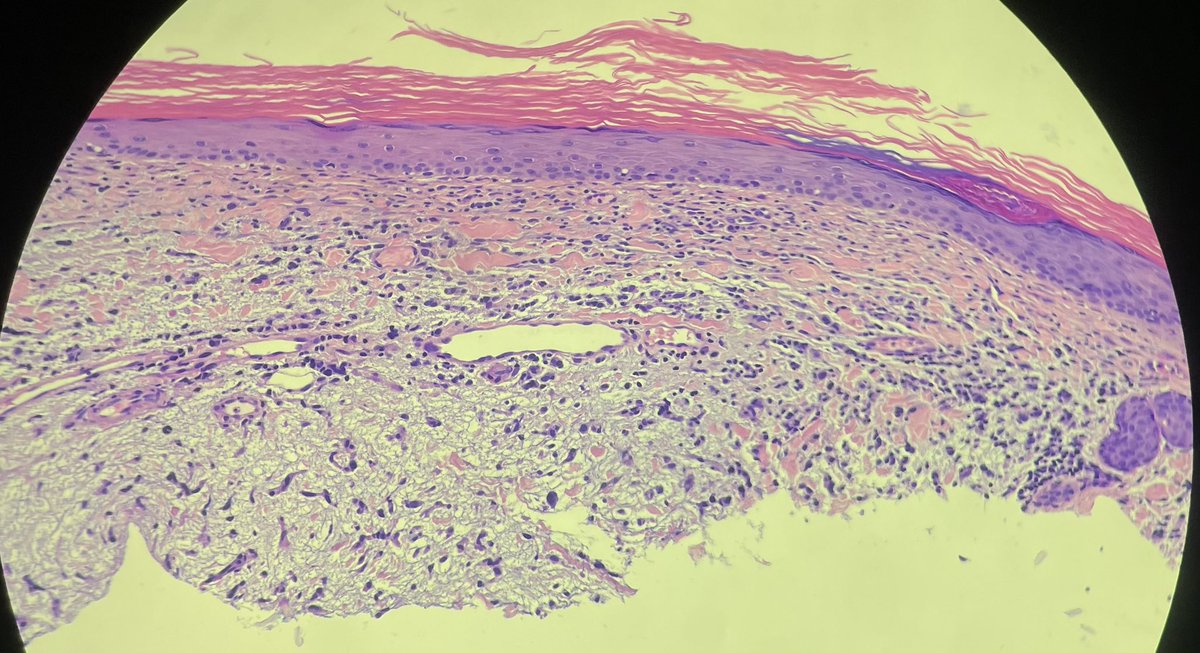

Calf. Elderly. Dx’s welcomed.

>70yo thigh. Eryrhematous nodule with hyperkeratotic scale. @mccalmo @HENRYY_MD Neg for CD34, sox10, cd30 (cd30 bc history said LyP, later found out it’s an autopopulate error). Focal cutaneous mucinosis? Cells are odd though.